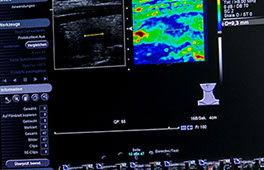

Die Elastografie ist eine besondere Ultraschalluntersuchung, in der die Festigkeit oder Elastizität eines Organes, oder einer Struktur in einem Organ, gemessen wird.

Mit der Elastografie ist nun ein wertvolles zusätzliches Merkmal, die Festigkeit eines Knotens, hinzugekommen: je härter, fester, unelastischer ein Knoten ist, desto wahrscheinlicher ist es, dass er aus bösartigen Zellen besteht (dies insbesondere dann, wenn die bereits bekannten Merkmale wie Echoarmut, unregelmäßige Begrenzung, ovale Form, Mehrdurchblutung, Kalkeinlagerungen zusätzlich vorhanden sind).

Bei der Elastografie der Leber wird vor allem auf diffuse Veränderungen des Lebergewebes geachtet: Je härter, fester Lebergewebe erscheint, desto mehr Bindegewebe ist in der Leber entstanden, desto eher entwickelt sich eine Leberzirrhose, also der Verlust funktionsfähiger Leberzellen zugunsten funktionsunfähiger Bindegewebszellen.